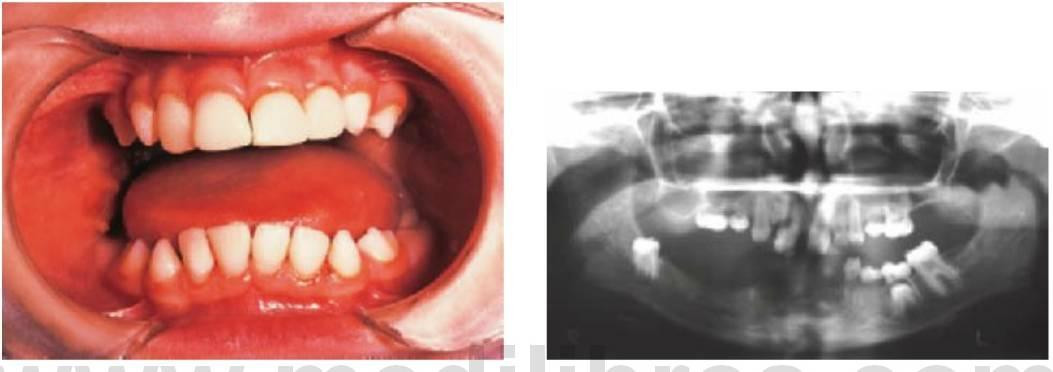

Los dientes supernumerarios surgen como resultado de una geminación de la lámina dental que se produce de forma esporádica o se heredan, como sucede con la displasia cleidocraneal (fig. 9.8).

La forma de los dientes puede recordar a la forma de las piezas normales (diente suplementario), es decir, incisiforme, caniniforme o molariforme; de no ser así, sería cónico o tuberculado.

Habitualmente se presenta como consecuencia del fallo en la erupción de uno o más dientes permanentes y en general presenta formas cónicas o tuberculadas.

- Erupción fallida o ectópica de un diente permanente (fig. 9.8B).

- A menudo erupcionan dientes cónicos que se pueden extraer con mucha facilidad (fig. 9.8A).

- Los dientes tuberculados o cónicos invertidos requieren extracción quirúrgica (fig. 9.8D) tan pronto como sea posible para permitir la erupción sin obstáculos del diente permanente.